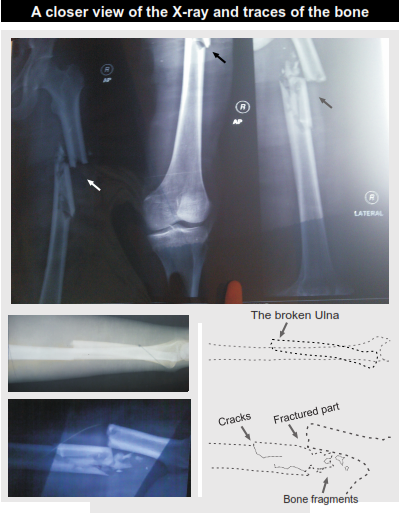

PICTORIAL REPRESENTATIONS